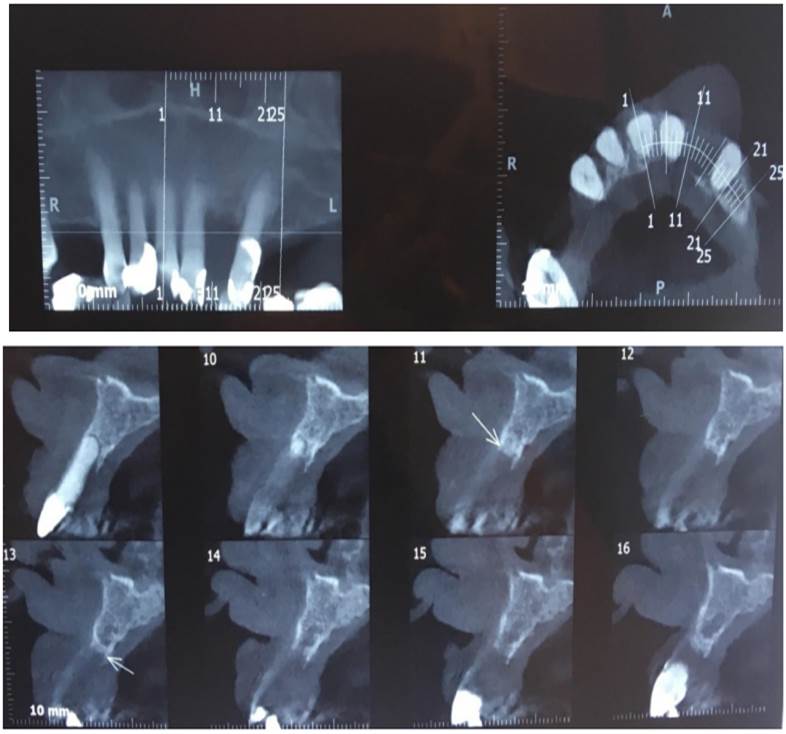

The first diagnostic hypothesis is a reactive inflammatory lesion, possibly a peripheral giant-cell granuloma. A CT was ordered to assess the underlying bone, presence or absence of bone resorption, or central lesion. The image shows that tooth 2.2 was missing and that there was chronic periodontal disease, with no bone alterations associated with the lesion to biopsy (figure 3).